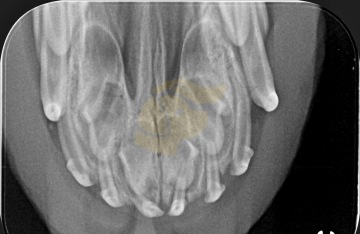

Intraorální rentgen – když zub není vidět

V případech, kdy některý zub není viditelný, ale není jasné, zda skutečně chybí, nebo je pouze neprořezaný, se používá intraorální rentgen. Tento typ snímkování umožňuje zjistit, zda se zub nachází v čelisti, ale z nějakého důvodu neprorazil dáseň (např. je impaktovaný nebo retenovaný).

Rentgen pomáhá určit:

Přítomnost zubu v čelisti.

Genetické chybění zubu (nezaložen).

Zda byl zub extrahován nebo ztracen v důsledku úrazu či nemoci.

Intraorální rentgen se provádí nejčastěji v sedaci nebo krátké anestezii, protože pes musí během zákroku zůstat zcela v klidu. Je to neinvazivní a velmi přesný způsob, jak doložit plnochrupost i v nejasných případech.